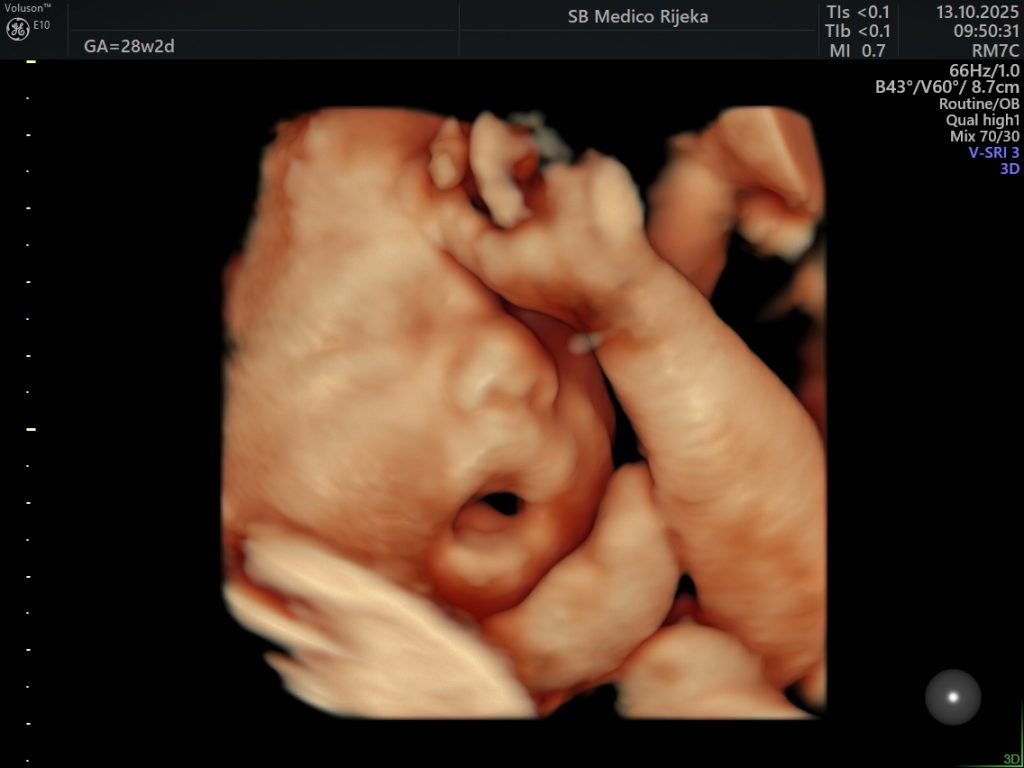

3D/4D ultrazvuk – trenutak koji ostaje zauvijek

Suvremeni 3D/4D ultrazvuk donosi novu dimenziju praćenja trudnoće. Omogućuje detaljniji prikaz razvoja djeteta prilikom svakog pregleda, a budućim roditeljima pruža priliku da na ekranu jasno vide lice svog djeteta, njegove pokrete i geste.

Iako je riječ o dijagnostičkoj metodi koja pomaže liječnicima u procjeni razvoja fetusa, taj pregled često ima i snažnu emocionalnu vrijednost, jer je to trenutak u kojem roditelji prvi put “upoznaju” svoju bebu.

U Medicu se 3D/4D ultrazvuk obavlja na najsuvremenijim uređajima visoke rezolucije koji omogućuju iznimnu jasnoću slike, a stručni tim ginekologa osigurava preciznu analizu i ugodno iskustvo pregleda.

Osim što doprinosi sigurnosti trudnoće, taj pregled mnogim roditeljima ostaje jedna od najljepših uspomena, jer je često to prvi osmijeh, zijevanje ili pokret njihove bebe koji imaju prilike vidjeti.